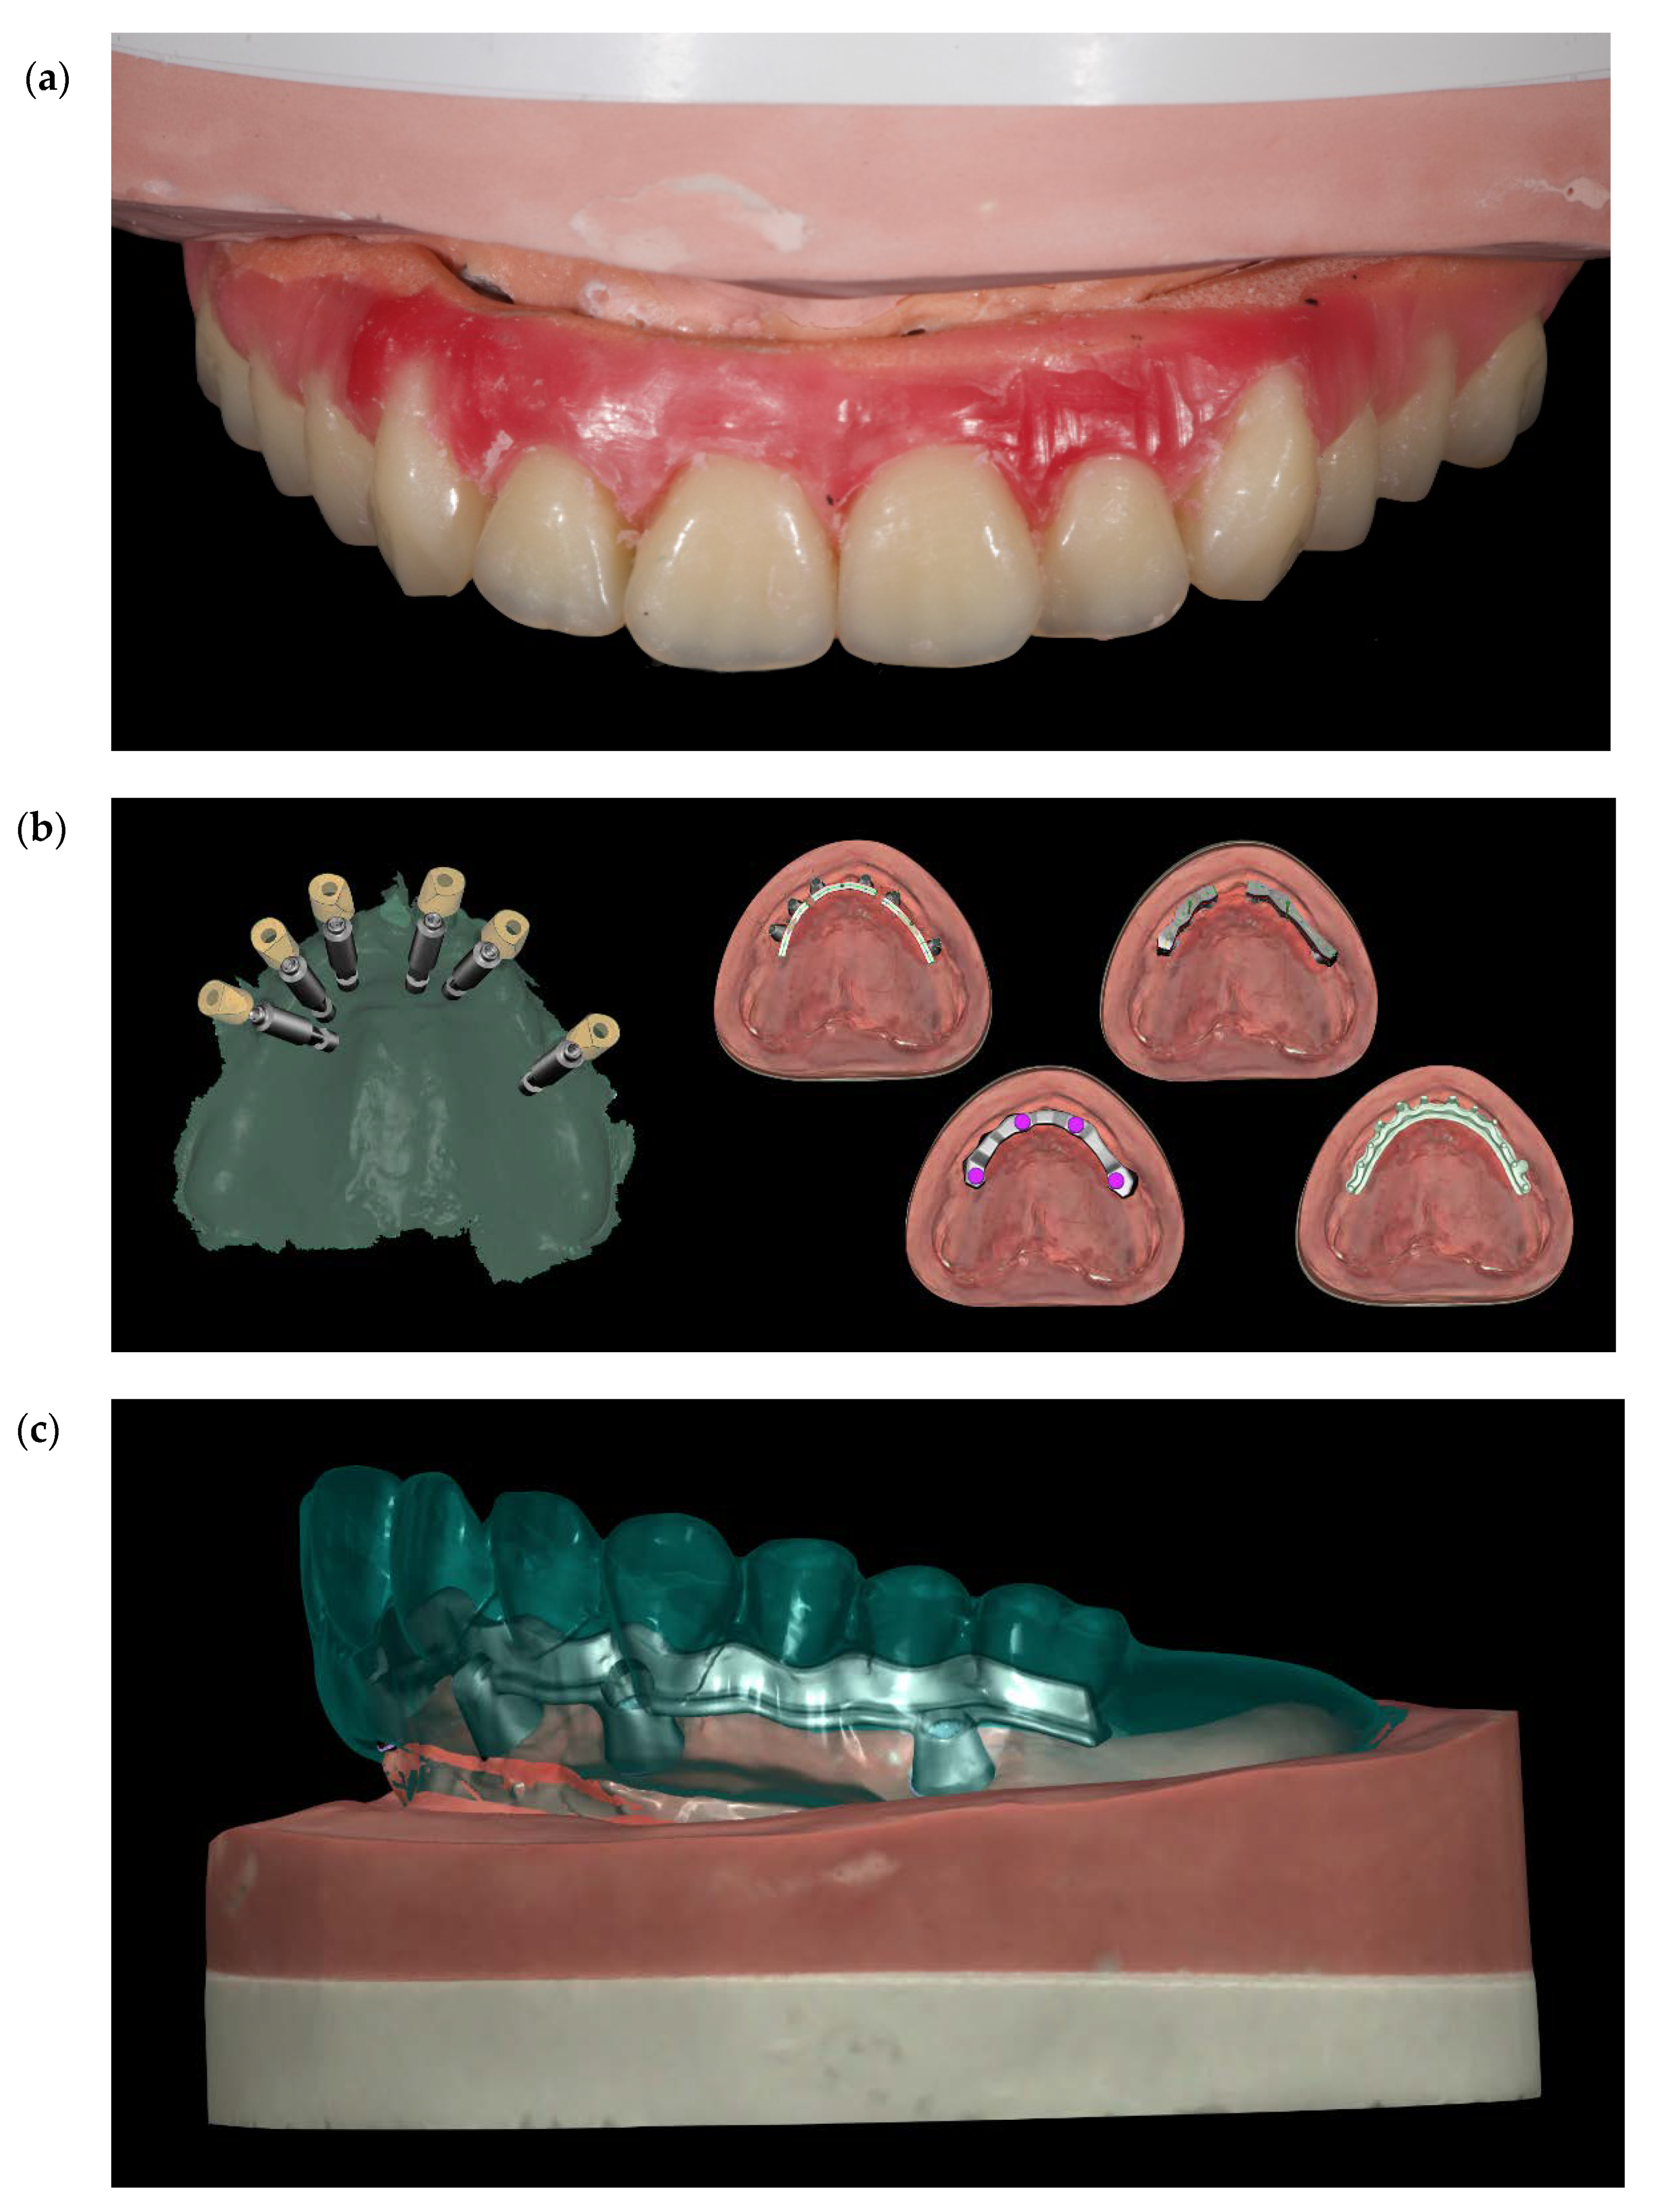

Figure 11.

(a) Set-up of the teeth. (b) Four different CAD projects (c) Single frame titanium bar CAD project.